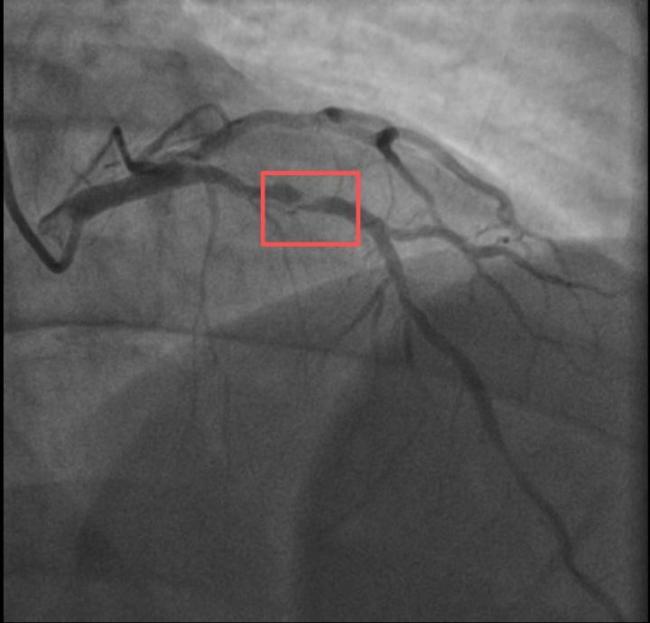

孙先生是一位羽毛球教练,身高173cm,体重约90KG。一年前,他因胸闷就诊时被查出心脏右冠中段、远端钙化斑块,以及心脏三支主要血管之一前降支中段60%狭窄。当时考虑到没有三高的危险因素(可能为早发冠心病家族史),孙先生坚信自己可以通过运动恢复健康,因此拒绝了介入治疗,只接受药物治疗。经过一年的努力,他的体重从96KG减到了90KG。然而,近日在带孩子练习羽毛球时,孙先生亲自上场挥杆仅10分钟左右,就因心前区剧烈绞痛被送进了急诊。医生分析,剧烈运动导致这位患者心脏的不稳定斑块破裂,进而造成前降支近段次全闭塞。所幸送医及时,孙先生的身体险情被化解。

另一位38岁的钱先生也有类似遭遇。钱先生的血糖一直偏高,服药后控制不佳,但年轻的他并没有太在意。周末,他和孩子爬了一座山,隔天就因突发胸骨中段压榨性疼痛被送到了急诊,最后被证实也是心梗——心脏三支主要血管之一回旋支远段次全闭塞。医生介绍,钱先生来院时血糖12.79mmol/L(正常空腹值应该在3.9~6.1mmol/L),甘油三酯也超标。三高是导致动脉粥样硬化的主要危险因素,在冠状动脉粥样硬化早期,血管狭窄可能并不严重,但在运动、情绪激动等情况下,心肌耗氧量增加,可能导致心梗等急性心肌缺血事件。所幸及时治疗,钱先生也转危为安。